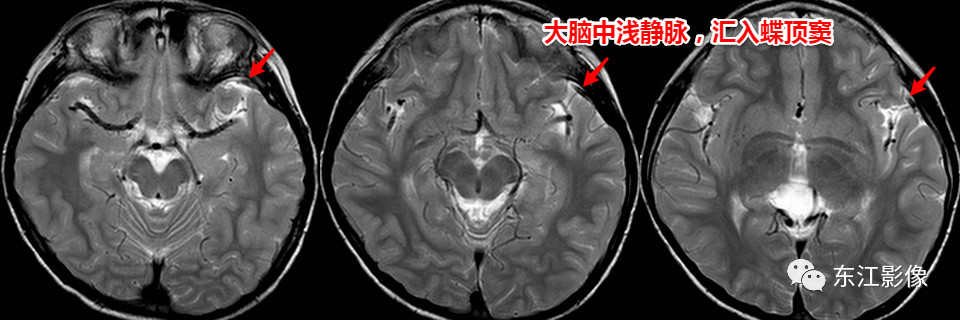

3)蝶顶窦

蝶顶窦左右成对,位于蝶骨小翼后缘两层硬脑膜之间,但存否不定。

接受附近硬脑膜静脉,有时接受硬脑膜中静脉的额支,开口于海绵窦前端。

图5 右侧蝶顶窦起始部折曲,容易误认为异常

两例大脑中浅静脉断层图像

图7 7岁男童,中间帆腔囊肿复查。左侧大脑中浅静脉,右侧Trolard静脉;中间帆腔囊肿

图8 22个月男童,头围偏大,发育未见异常,神经系统体征(-)。既往MR:先天性蛛网膜下腔增宽。右侧大脑中浅静脉,双侧Labbe静脉;终末带。